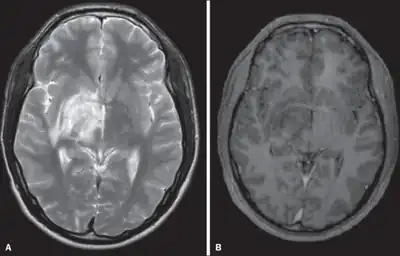

- Koçer, N; Islak, C; Siva, A; Saip, S; Akman, C; Kantarci, O; Hamuryudan, V (Jun–Jul 1999). "CNS involvement in neuro-Behçet syndrome: an MR study". AJNR. American Journal of Neuroradiology. 20 (6): 1015–24. PMC 7056254. PMID 10445437. Archived from the original on 2023-09-30. Retrieved 2023-09-22. Archived 2023-09-30 at the Wayback Machine